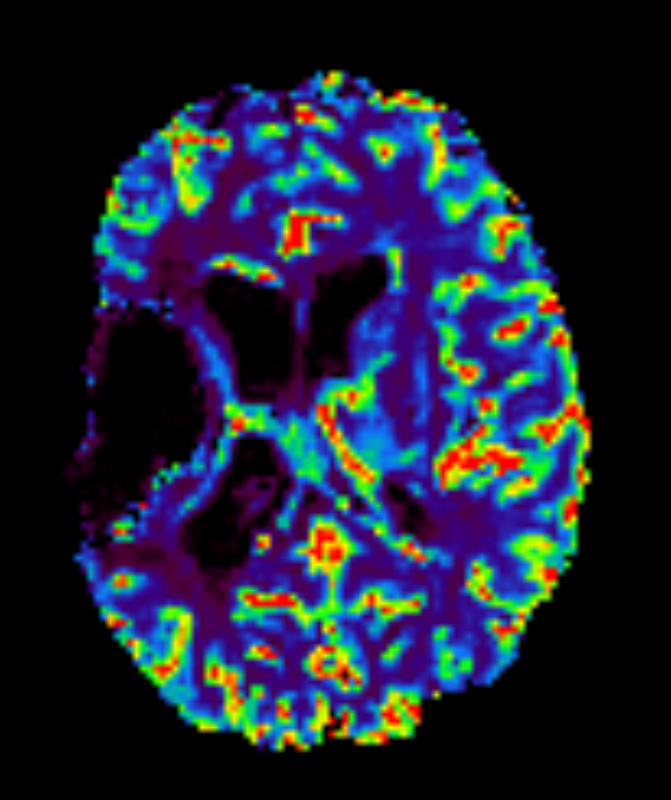

Brain glioblastoma, post-operative

Patient who was operated on glioblastoma

Axial T2* Perfusion - rCBF